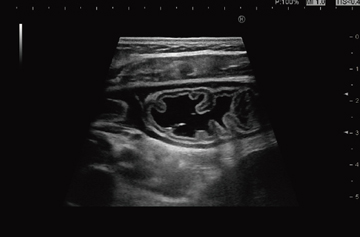

新開発のUltra BEU(Ultrasound Broadband Engine 2nd Generation)による信号処理回路の高速化により,より進化したHI REZ(High Resolution Imaging)を搭載した(図1)。HI REZは,超高速アルゴリズムを用いて,リアルタイムに数万回の空間画像処理を実施する高精細画像適応型フィルタ技術である。構造物の抽出,組織の強調を行い,超音波画像に特有なアーチファクトであるスペックルノイズを低減させることで,コントラスト分解能を向上させ,より明瞭に組織構造を描出する。また,全素子送受信技術やLow Noise Amplifier,Adaptive Enhanceなどの技術と合わせることで,クリアで美しい画像を追究している。